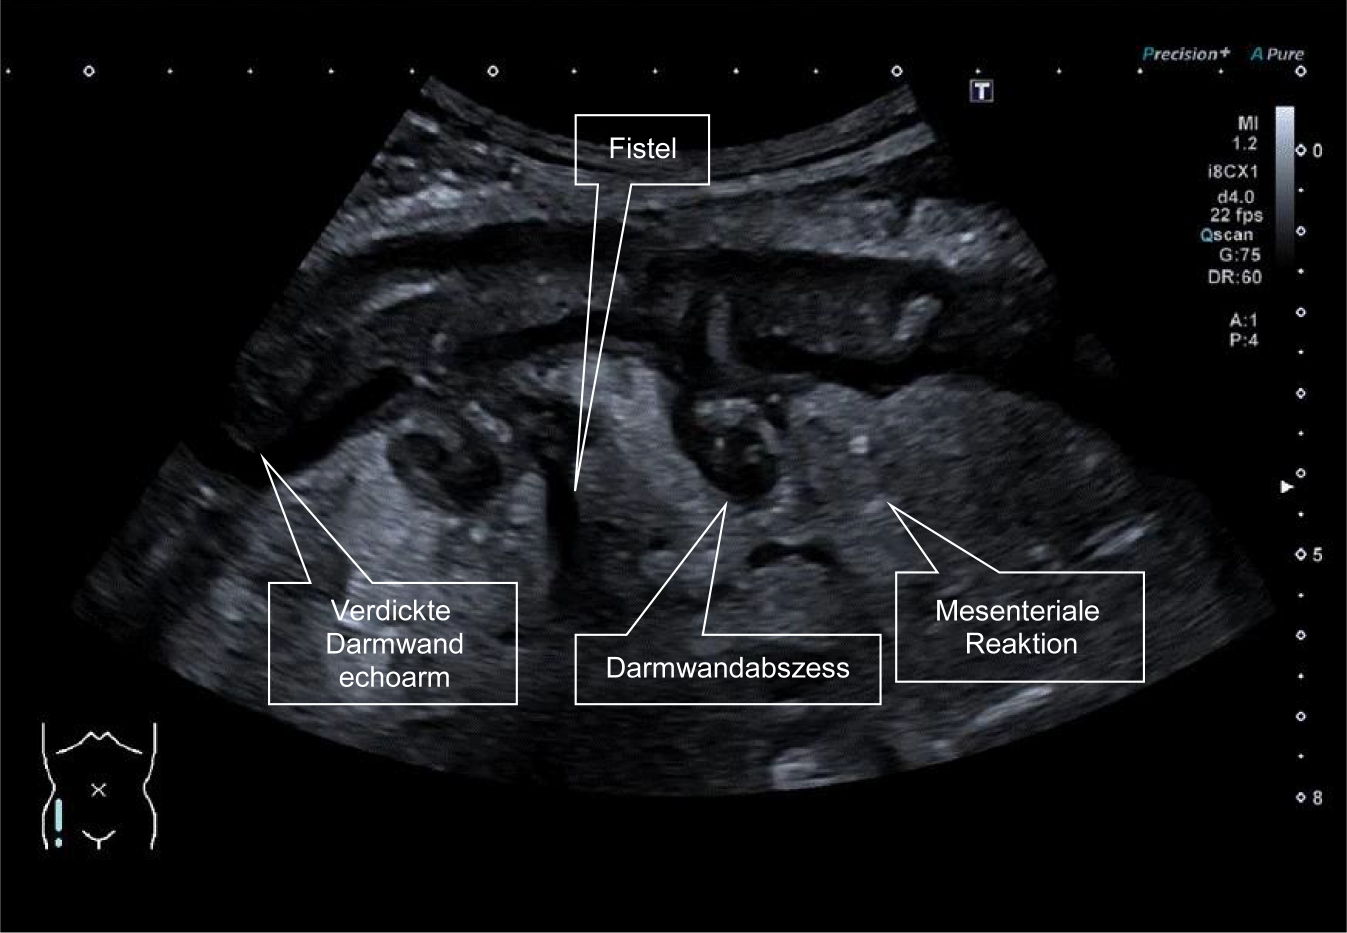

Abb. 3

43-jähriger Patient mit langjährigem Morbus Crohn des Kolons. (Zuletzt seit 2 Jahren ohne Medikation, bei selbstständigem Absetzen von Ustekinumab. Seit 2 Wochen zunehmende Unterbauchschmerzen und intermittierend Fieber. Die Darmwand des Colon ascendens ist deutlich verdickt, sie ist echoarm als Zeichen der Entzündung. Die Schichtung ist aufgehoben, das Lumen ist komprimiert. Es zeigt sich eine mesenteriale Reaktion im Sinne einer echoreichen Gewebevermehrung um das Kolon. In diesem Bereich dunkle Areale: Fisteln, die vom Kolon ausgehen und zu drei kleinen Abszessen geführt haben)

Bild vergrößern

Abb. 4

Derselbe Patient, Darstellung mit dem 10-MHz-Schallkopf. Deutlich lässt sich ein Abszess im mesenterialen Gewebe abgrenzen (Pfeil). Zudem zeigt sich parakolisch freie Flüssigkeit